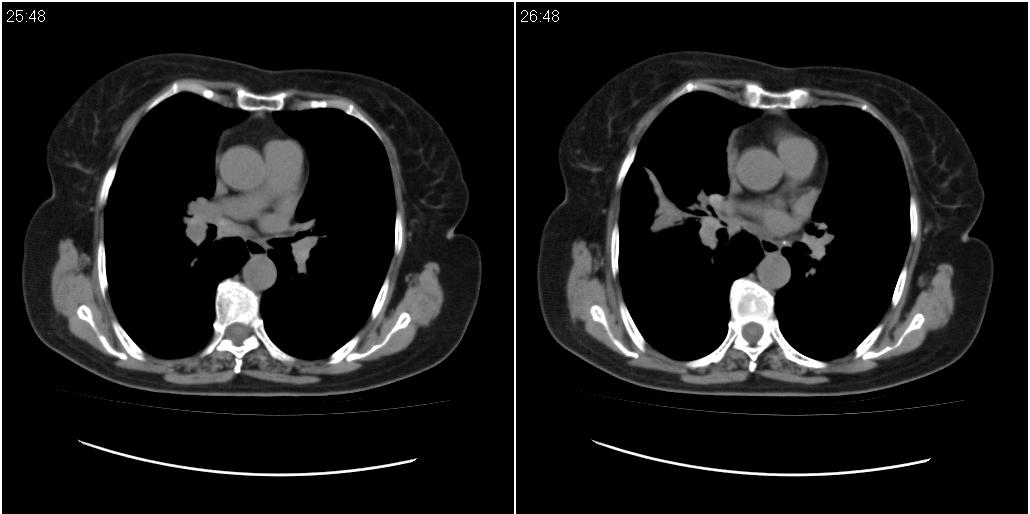

女性,72岁。去年9月份发现肺部病变,诊为肺结核并进行正规治疗至今,但复查后发现ct表现几乎没有变化。

右中间段支气管局限性狭窄,右中叶支气管亦稍显狭窄,但并未见明显占位表现,半年多了,无变化也许是好事,可能为炎性狭窄,建议继续随访。

双肺继发型tb并右中叶内膜tb,轻度支扩,左下胸膜肥厚粘连。

右中叶炎性改变,支气管狭窄但较光滑,占位可能性不大。

双肺继发性肺结核并右肺中叶节段性肺不张,左下胸膜肥厚粘连。

右肺中叶节段性肺不张,考虑结核或慢性炎症,建议做纤支镜检查。

双肺继发性肺结核并右肺中叶节段性肺不张